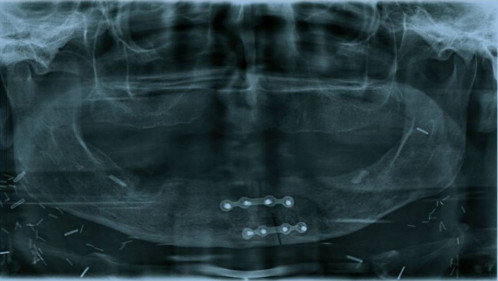

Makroskopie - intraoral präoperativ